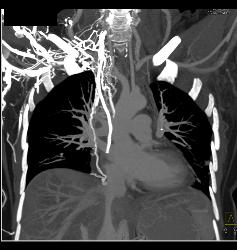

SVC Occlusion With Huge Collaterals and Thrombus Into Right Atrium